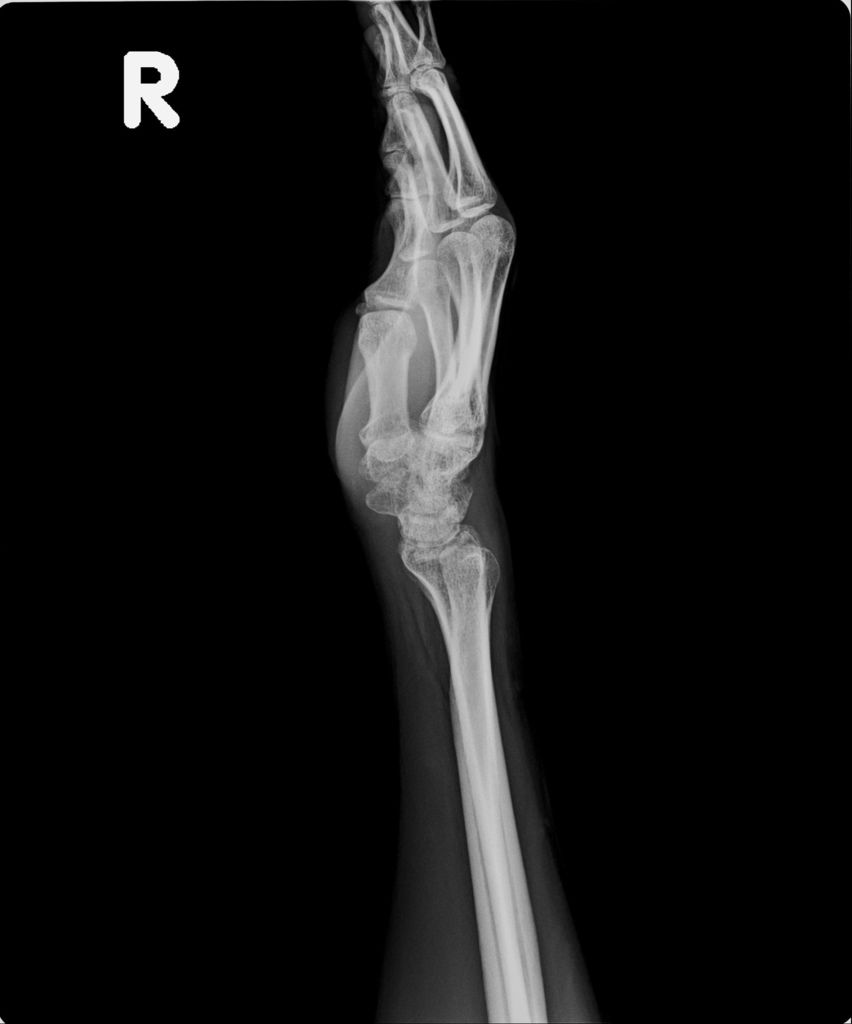

右手X光↓

進入門診前,我自認為手比腳恢復還快,因為比起一開始,手指比較能出力了,手腕可轉動的範圍也變大了。腳因一直用副木石膏固定住,不能動,所以也不知恢復多少。進入門診後,黃醫師說斷裂的骨頭都沒移位。手沒什麼進展(骨頭不會長那麼快),腳的部份下回再來復診時,可能會恢復的較快了。

手沒什麼進展這件事,讓我比較吃驚,詢問黃醫師,手如果也改用副木,會不會比較好,黃醫師說,他個人是認為沒什麼差。他看著X光片照出來的結果,說開刀或不開刀他覺得都差不多。